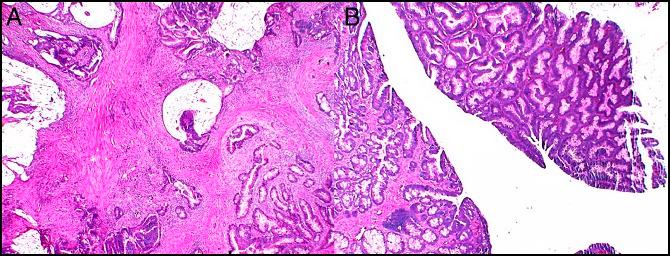

Ileocecal intussusception caused by two different tumors - which is the culprit lesion? A case report.

World J Clin Cases. 2020 May 26;8(10):2044-2049. doi: 10.12998/wjcc.v8.i10.2044.